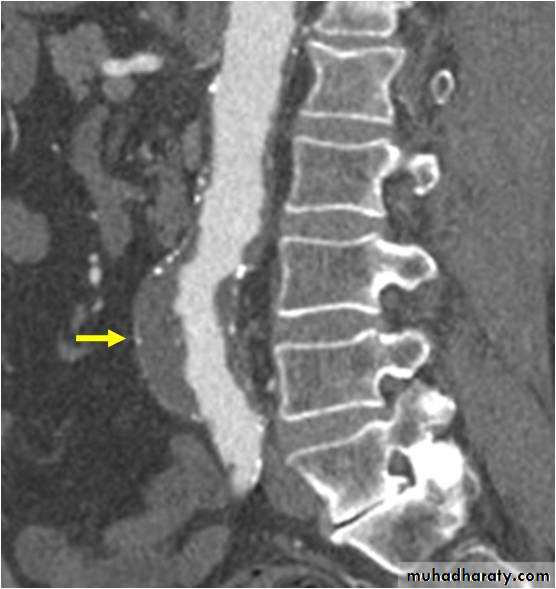

Expanding abdominal aortic aneurysm

Ruptured abdominal aortic aneurysm